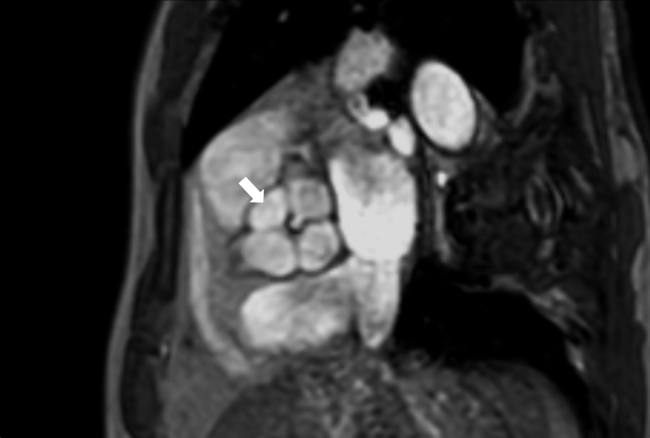

Cardiac magnetic resonance imaging (CMRI) was done to assess the cardiac function, evaluate the aortic valve morphology, and analyze the severity of AR. On CMRI, a quadricuspid aortic valve with 3 equal-sized cusps and 1 smaller cusp with 4 sinuses was well appreciated, along with severe aortic regurgitation and mild left ventricular dysfunction (Figure 1, Videos 1 and 2). The ascending aorta was normal. The patient underwent surgical aortic valve replacement with a coronary artery bypass graft to the LAD. He is doing well at 6-month follow-up.